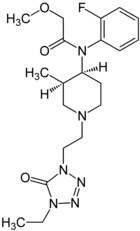

Anilidopiperidines